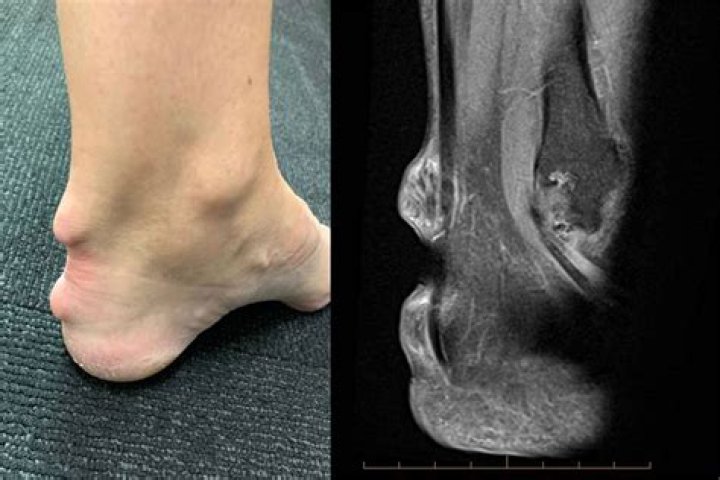

Plant thorn synovitis, also known as plant thorn arthritis, is a rare and commonly overlooked cause of arthritic disease. This disease is attributed to a granulomatous inflammatory response to retained plant thorn fragments following a puncturing plant thorn injury.

How do you know if you have plant thorn arthritis?

The diagnosis of plant thorn arthritis is made by detection of a piece of thorn within the joint by imaging tests or surgical removal and identification of the thorn fragments. The involved joint may be swollen, painful, reddened, stiff, and may have a reduced range of motion.

What is the prognosis of plant thorn arthritis? Once a synovectomy for plant thorn arthritis has been performed, the joint tends to heal well without residual problems. The sooner the synovectomy is performed, the better the outcome as chronic joint inflammation can risk damage to cartilage of the joint.